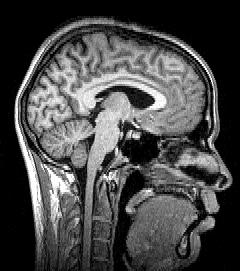

Towards a high-resolution, implantable neural interface

The goal of The Neural Engineering System Design program is developing an implantable system able to provide precision communication between the brain and the digital world.

Hacking the human brain

One of the greatest challenges facing artificial intelligence development is understanding the human brain and figuring out how to mimic it.